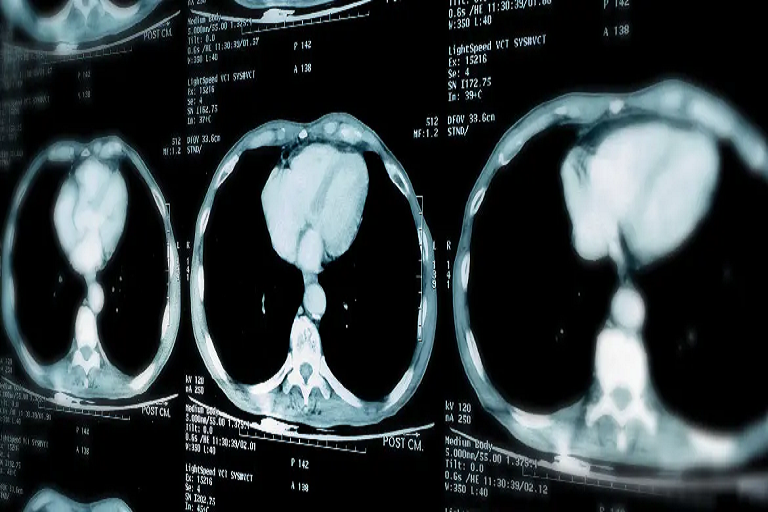

In the Cancers article, researchers led by Vincenza Granata evaluated HealthMyne’s technology as a quantitative imaging decision support tool for radiomic analysis of lung adenocarcinoma in chest CT scans. Researchers analyzed radiomic biomarkers to predict Overall Survival (OS) and Progression Free Survival (PFS) time.

Researchers segmented each patient’s lesion leveraging HealthMyne’s advanced imaging analytics solution to extract 573 radiometric metrics from the cohort images to predict OS and PFS time. Researchers found that 19 radiomic features were significant for predicting OS and 108 radiomic features for predicting PFS time.